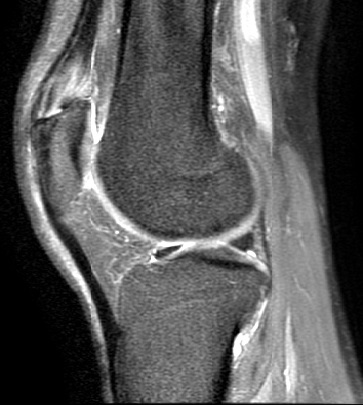

An 80 year old female presents to your office with a left ring finger deformity after a fall one week ago. She initially went to urgent care and xrays were unremarkable for a fracture (Figures 1 and 2). A photo of her left ring finger is shown in figure 3. On physical exam the left ring finger is in hyperextension at the PIP joint and flexion at the DIP joint. She able to flex her PIP joint with full motion. What is the best treatment option?